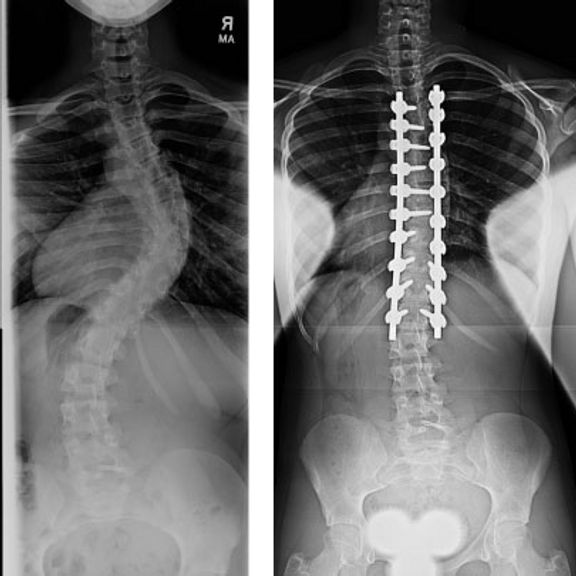

Some severe cases of scoliosis may require surgery to halt the progression of the spinal curvature and correct spinal balance. The most common type of scoliosis surgery is spinal realignment and fusion. Modern day techniques are very safe and effective at correcting scoliosis in the growing child.